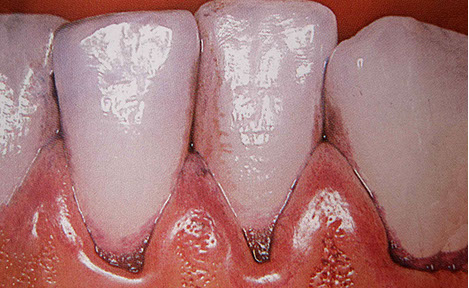

If the consumption of nicotine, coffee or red wine has led to discolouration, the resulting dark deposits are gently cleaned with a high-pressure powder-water jet (Airflow®) before all tooth surfaces are thoroughly polished smooth.

Finally, all tooth surfaces are coated with fluoride varnish for better protection against caries. The fluoride hardens the enamel and protects the tooth against bacterial acid attacks. This reduces the risk of tooth decay and remineralises pre-existing minor decalcifications of the enamel surface.